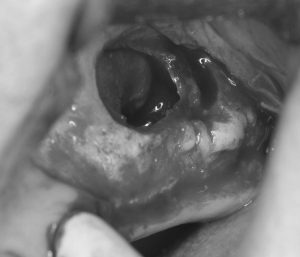

耳鼻科医とタイアップしたサイナスリフト10年経過 2022 1/31 臨床アラカルト 2017年8月14日2022年1月31日 サイナスリフト前と手術直後(写真をクリックして拡大してみてください。写真右上の副鼻腔内造骨術前後です。) Exif_JPEG_PICTURE サイナスリフト前とインプラント術後のCT サイナスリフト術中。窓開けし膜を挙上し、骨補填材を入れ、人工膜を外側に置いて保護します。 写真の右端の奥2本がインプラントです。本ケースは横浜市立大学耳鼻科に対診し行いました。 臨床アラカルト サイナスリフト インプラント 骨造成 よかったらシェアしてね! URLをコピーしました! URLをコピーしました! 両側サイナスリフト9年経過 造骨処置 関連記事 学んだばかりの技術を活かす(歯周組織再生療法) 2026年5月11日 患者さんから学ぶ 2026年4月20日 80歳の方の矯正 2026年3月24日 学んだ事を早速応用しました 2026年3月10日 下顎前歯部インプラント 2026年2月17日 トラブルシューティング 2026年2月4日 80歳で矯正を希望された方 2025年12月26日 貼物作り 2025年11月27日 コメント コメントする コメントをキャンセルコメント ※ 名前 ※ メール ※ サイト 次回のコメントで使用するためブラウザーに自分の名前、メールアドレス、サイトを保存する。 上に表示された文字を入力してください。